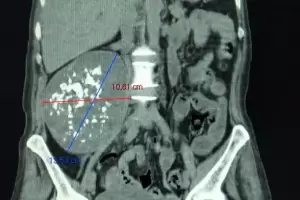

Médicos del "San Juan Bautista" extirparon un tumor gigante de una paciente

La exégesis fue sobre una masa tumoral de 10.61 x 13.50 cm. Los profesionales que intervinieron a la mujer de 58 años, marcaron que esta evoluciona y está compensada. La cirugía fue realizada por el equipo de Cirugía Oncológica y de Cabeza y Cuello, de reciente creación, y grandes logros a la fecha.